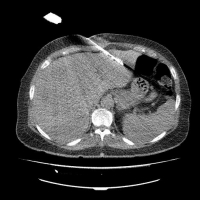

Bilder: CT-gestützte Radiofrequenzablation einer Lungenmetastase (Pfeil, links), CT-gestützte Mikrowellenablation einer Lebermetastase (rechts).